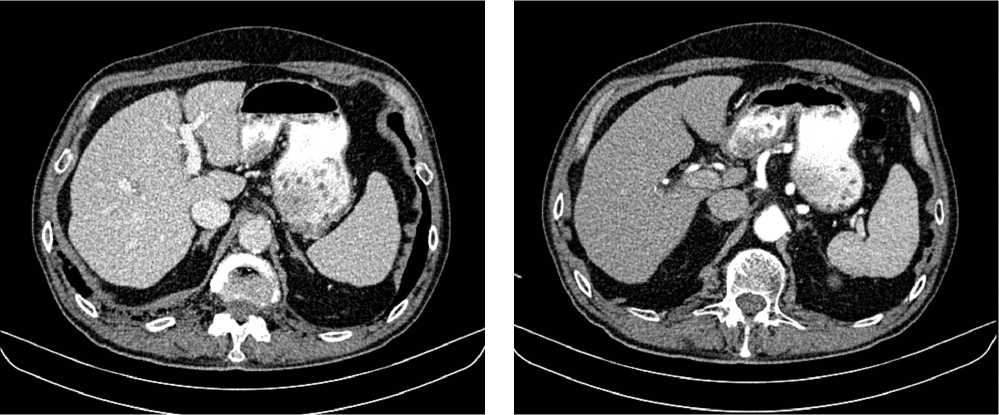

В результате обследования был установлен диагноз рака антрального отдела желудка (c)T4аN3вM1. По решению онкологического консилиума, учитывающего молекулярно-генетический профиль опухоли, а также возраст пациента, выраженность сопутствующей патологии (в анамнезе острое нарушение мозгового кровообращения (ОНМК), острый инфаркт миокарда (ОИМ), фибрилляция предсердий (ФП), постоянная форма), ограничивающей проведение ПХТ, была начата ИТ 1 линии пембролизумабом. С сентября 2019 г. по декабрь 2021 г. проведено 29 циклов ИТ 1 линии по схеме пембролизумаб в монорежиме с максимальным эффектом частичный регресс (рис. 4). Осложнений лечения не зарегистрировано.

Рис. 4. Частичный регресс по данным компьютерной томографии органов брюшной полости на фоне иммунотерапии пембролизумабом у пациента 81 года с диагнозом метастатический рак желудка с признаками микросателлитной нестабильности (декабрь 2021 г.; выживаемость без прогрессирования составила 25+ мес.)

Fig. 4. Partial response according to abdominal CT scan during immunotherapy with pembrolizumab in an 81-year-old patient diagnosed with MSI-H metastatic gastric cancer (December 2021; progression-free survival was 25+ months)

Для оценки метаболической активности остаточной опухолевой ткани выполнено позитронно-эмиссионная томография, совмещенная с компьютерной томографией (ПЭТ-КТ) в марте 2022 г., по результатам которого выявлено умеренное повышение уровня метаболической активности в проекции выходного отдела желудка и двух ЛУ брюшной полости, без значимой динамики в сравнении с предшествующим исследованием.

Для морфологической оценки патоморфологического регресса выполнена эзофагогастродуоденоскопия — эндоскопические признаки полного регресса опухоли. По результатам гистологического исследования, опухолевых клеток не выявлено.

Пациент находится под динамическим наблюдением без признаков прогрессирования процесса по настоящее время (выживаемость без прогрессирования составила 25+ мес.).